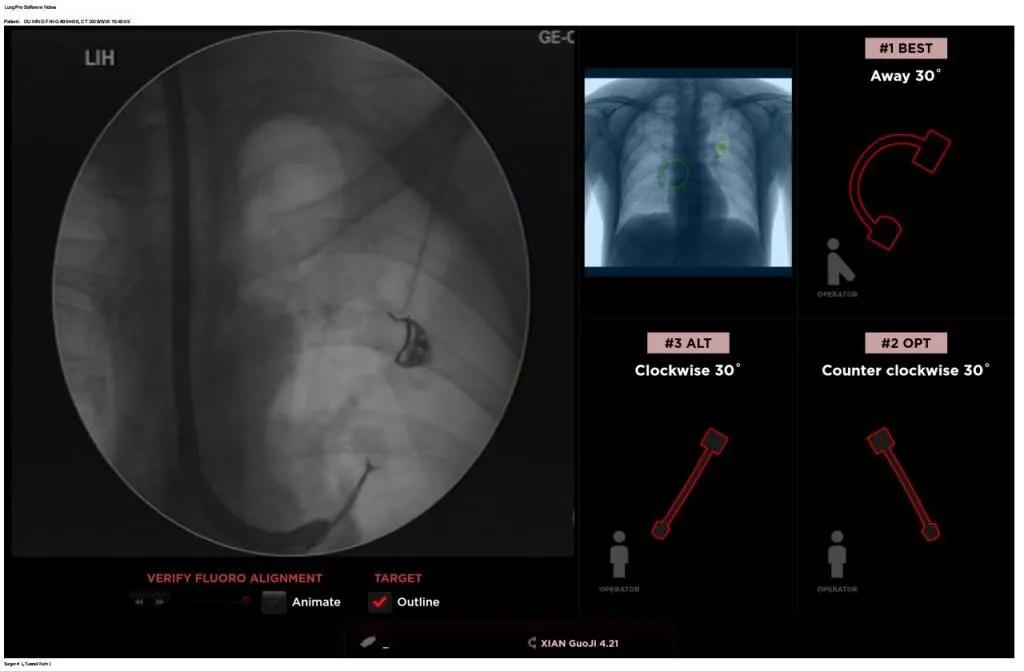

近日,西安國際醫(yī)學(xué)中心醫(yī)院胸科醫(yī)院歐陽海峰副院長完成西北地區(qū)首例LungPro全肺導(dǎo)航系統(tǒng)引導(dǎo)下經(jīng)支氣管鏡跨肺實(shí)質(zhì)肺外周結(jié)節(jié)活檢術(shù)。

經(jīng)過充分的討論后,歐陽海峰副院長決定為患者實(shí)施LungPro全肺導(dǎo)航系統(tǒng)引導(dǎo)的經(jīng)支氣管跨肺實(shí)質(zhì)肺外周結(jié)節(jié)活檢術(shù)。Broncus導(dǎo)航系統(tǒng)LungPro具有全球領(lǐng)先獨(dú)創(chuàng)的BTPNA技術(shù)(支氣管鏡下跨結(jié)節(jié)抵達(dá)術(shù)),可以實(shí)現(xiàn)對氣道外周孤立性肺小結(jié)節(jié)的精準(zhǔn)定位,建立直接通往氣道外病變部位的通道,以實(shí)現(xiàn)全肺的診斷及后續(xù)治療。這項(xiàng)技術(shù)不僅彌補(bǔ)了現(xiàn)有支氣管鏡技術(shù)由于受限于病變部位是否有氣道可通向以及無法準(zhǔn)確定位病變部位而造成的較低診斷率,同時(shí)還彌補(bǔ)了CT引導(dǎo)下經(jīng)胸穿刺(TTNA)無法適用于某些特定部位如中央及肩胛骨等結(jié)節(jié)的問題,并且還避免了經(jīng)胸穿刺給患者帶來氣胸、出血的高風(fēng)險(xiǎn),可有效提高肺部結(jié)節(jié)及早期肺癌診斷陽性率,亦可用于早期肺癌的射頻消融或微波治療,具有微創(chuàng)、安全、同期雙肺診療等優(yōu)勢。

團(tuán)隊(duì)術(shù)前進(jìn)行了精心的準(zhǔn)備,通過高分辨率CT建立了導(dǎo)航路徑,在麻醉科手術(shù)室的配合下,借助LungPro引導(dǎo)順利的確定了病灶部位、建立隧道并實(shí)施活檢,術(shù)后患者恢復(fù)順利出院。